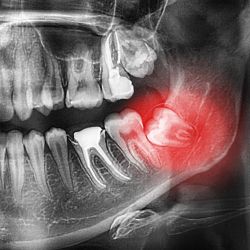

La buena noticia es que la cirugía de muela del juicio es segura y muy frecuente. Con anestesia local y técnicas modernas, la mayoría de los pacientes se recuperan sin complicaciones y evitan problemas como dolor, infecciones o apiñamiento dental.